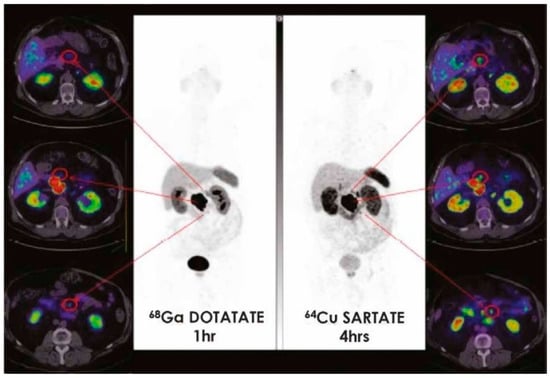

At days 1 and 2 of the study protocol, PET/CT was performed after 30 min, 1 h, 4 h and 24 h after 64Cu-SarTATE administration plus safety assessment. No significant adverse reactions were registered, except for mild infusion-related events in three subjects. Of note, 64Cu-SarTATE showed intense accumulation in tumor lesions at each time point of acquisition, with comparable or superior detection rates (i.e., number of lesions detected) with respect to 68Ga-DOTATATE, especially in the liver. Figure 3 illustrates the diagnostic performance of 64Cu-SarTATE with respect to 68Ga-DOTATATE in NET metastatic patients.

Figure 3.

CL01-trial. High lesion contrast on 64Cu-SarTATE images at 4 h (right) better defines regional nodal disease than 68Ga-DOTATATE images at 1 h (left) in patients with pancreatic primitive neuroendocrine tumors (Images courtesy of Clarity Pharmaceuticals).